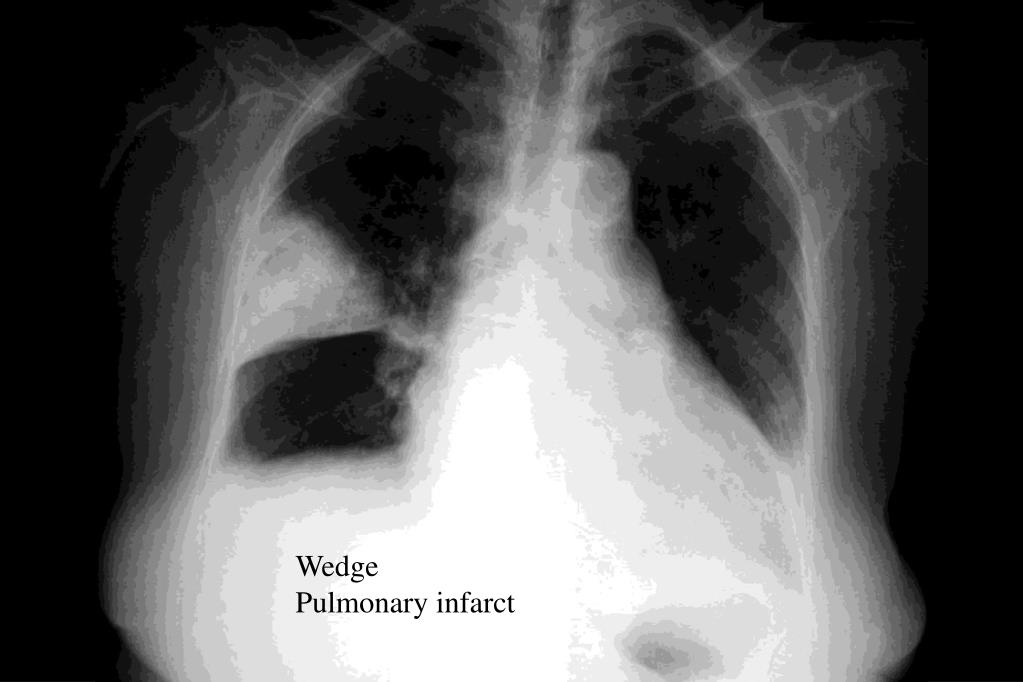

PPT Chest XRays Every Resident Should Know Part 2 PowerPoint Cat Under The Rug Sign Radiology The characteristic features of the density are:. See table 1 for differential diagnosis for common lung. Some of these are specific to a disease, whereas. Several metaphoric chest ct scan signs have been described linking abnormal imaging patterns to lung diseases. Expanding lesions of structures in the chest wall give rise to this sign. Retrograde urethrography (rug) and voiding cystourethrography. Cat Under The Rug Sign Radiology.

PPT Chest XRays Every Resident Should Know Part 2 PowerPoint Cat Under The Rug Sign Radiology See table 1 for differential diagnosis for common lung. Several metaphoric chest ct scan signs have been described linking abnormal imaging patterns to lung diseases. This sign helps to recognize the site of the lesion. Radiographic lung patterns in dogs and cats. Retrograde urethrography (rug) and voiding cystourethrography (vcug) are complementary studies for evaluating the male urethra. The characteristic features. Cat Under The Rug Sign Radiology.